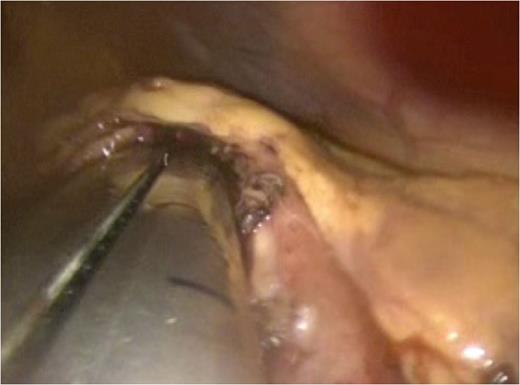

Attention was then turned to the pseudocyt. The stomach was seen draped over the pseudocyst, with small bowel adherent to its greater curvature. Therefore, we decided to use an anterior approach. A gastrostomy was created to open the body of the stomach (Fig. 3). This allowed the scope to enter the gastric lumen. The area of maximal pointing of the pseudocyst into the posterior wall was identified. A second gastrostomy was created at the posterior stomach wall (Fig. 4) and this was developed to enter and then decompress the pseudocyst lumen. A 60 mm Endo-GIA stapler was introduced into the tract (Fig. 5) and used to create a sturdy anastomosis between the lumina of pseudocyst and stomach (Fig. 6). The hanging manoeuvre was then used to suspend the anterior stomach wall in order to facilitate closure with the endo-GIA stapler (Fig. 7). The single ‘S’ incision in the abdomen was closed in layers. No cultures were taken since there was no clinical or biochemical evidence of infection.

Cystogastrostomy was performed using the anterior approach. An incision was made in the anterior wall of the body of the stomach to allow entry into the gastric lumen.